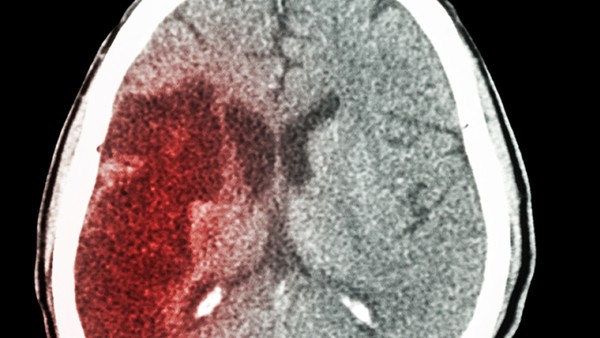

1、脑梗塞手术不一定需要开颅,只有一部分脑梗塞患者需要开颅手术。这部分患者是由于大面积脑梗,导致严重脑水肿,患者颅内压力急剧上升,侧脑室受压,中线移位,甚至神志不清,有脑疝形成的前兆。如果不及时开颅去骨瓣减压手术治疗,患者会形成小脑幕切迹疝,导致严重昏迷,威胁到患者生命安全。

大面积小脑梗塞手术适应症包括目前一般认为保守治疗无效、患者病情加重、意识障碍加深或具有减压性手术治疗的指征,可行脑室外引流加枕骨下减压术,切除梗塞组织和小脑扁桃体减张缝合硬膜。一般认为大面积脑梗死后24小时内手术,可以降低死亡率提高预后。